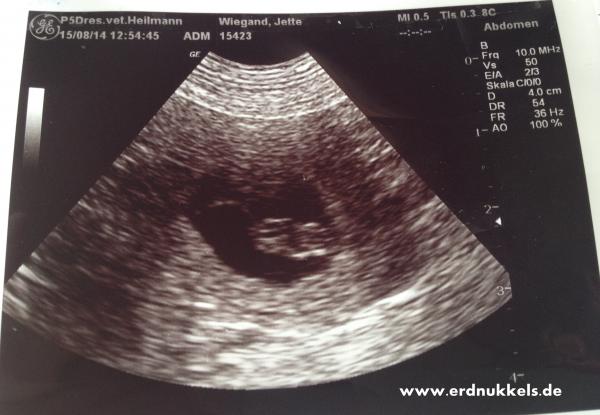

15.08.14

Welch eine riesen große Freude!!!!

Jette ist trächtig und somit ist unser A-Wurf auf dem Weg!!